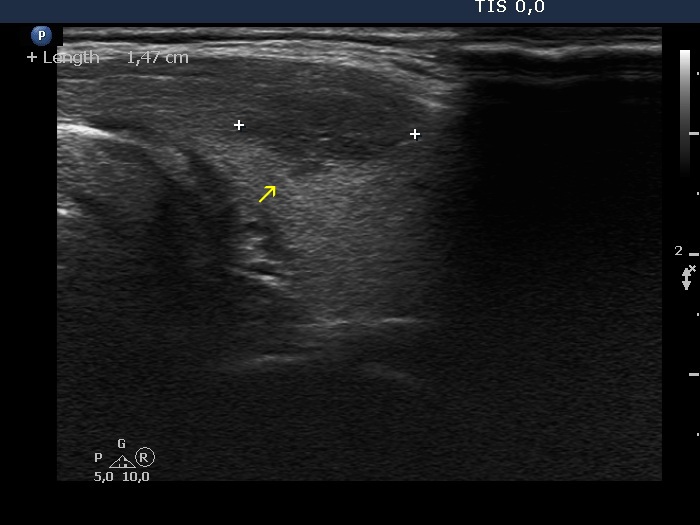

Papillary carcinoma (histology) - case conp006

Transverse scan

Longitudinal scan

The tumor spreads into the normal parenchyma with elongated projections which have sharp edges (yellow arrows).